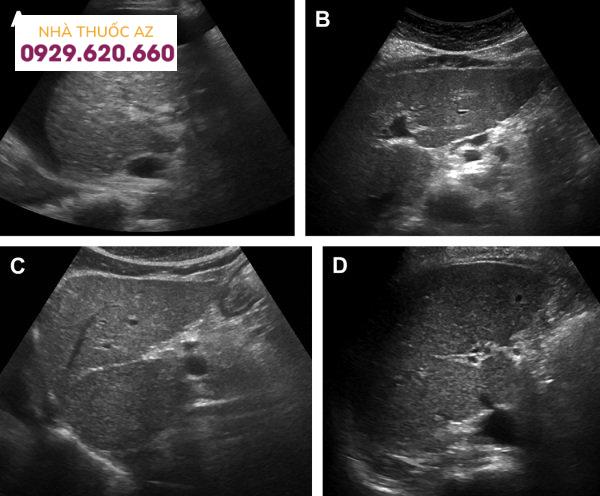

Hình ảnh xơ gan: Siêu âm cắt đứng dọc (A) bộc lộ nốt bề mặt, dịch ổ bụng và nhu mô thô. Các ảnh đứng dọc cho thấy (B) phì đại phân thùy ngoài, (C) phì đại thùy đuôi, và (D) teo thùy phải.